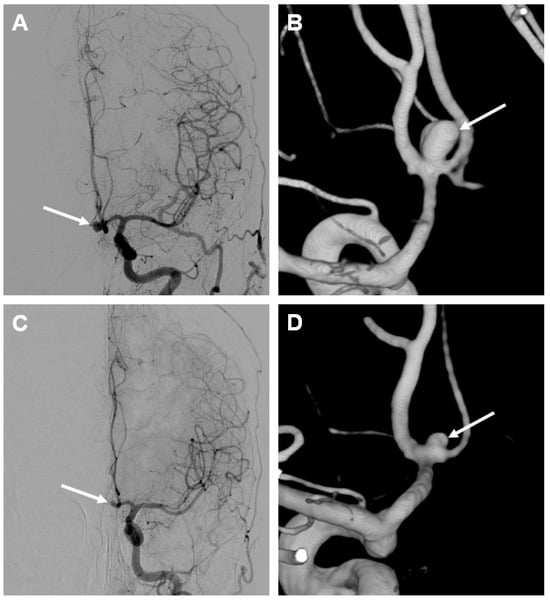

Case Description

2.5. Outcome and Follow-Up